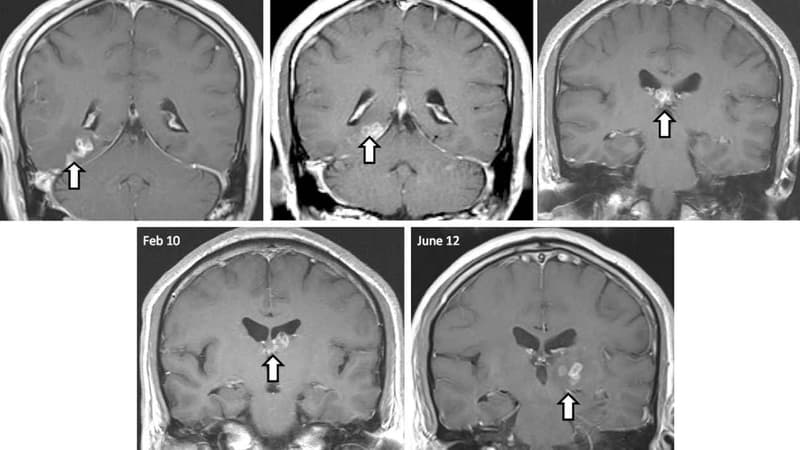

Les accidents vasculaires cérébraux (AVC) provoqueraient un vieillissement de huit ans du cerveau, selon une étude menée par des scientifiques américains de l'université du Michigan. Les principales fonctions traumatisées étant la mémoire et la vitesse de réflexion.

Cette étude, publiée dans la revue Stroke, s'est portée de 1998 à 2012 sur 4.900 hommes et femmes âgées de plus de 65 ans et victimes d'AVC. Le vieillissement serait dû à de fortes lésions cérébrales.